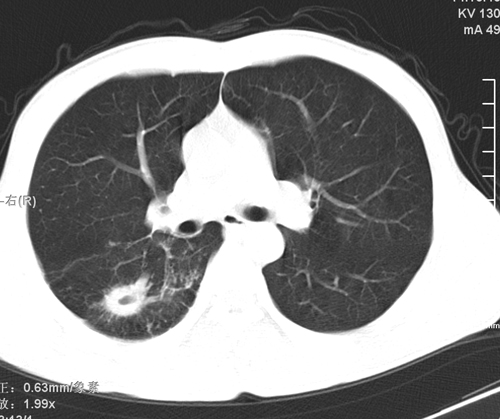

标题: CT24548:男 31 咳嗽 咯血一天 行CT检查 [打印本页]

标题: CT24548:男 31 咳嗽 咯血一天 行CT检查

ct考虑结核 但化验结果示白细胞总数 淋巴均正常,血沉7mm/h不快,请看看结核 支扩还是其他

右肺上叶尖端,后段下叶背段结核伴空洞形成

好发部位+多种性质病灶=典型tb